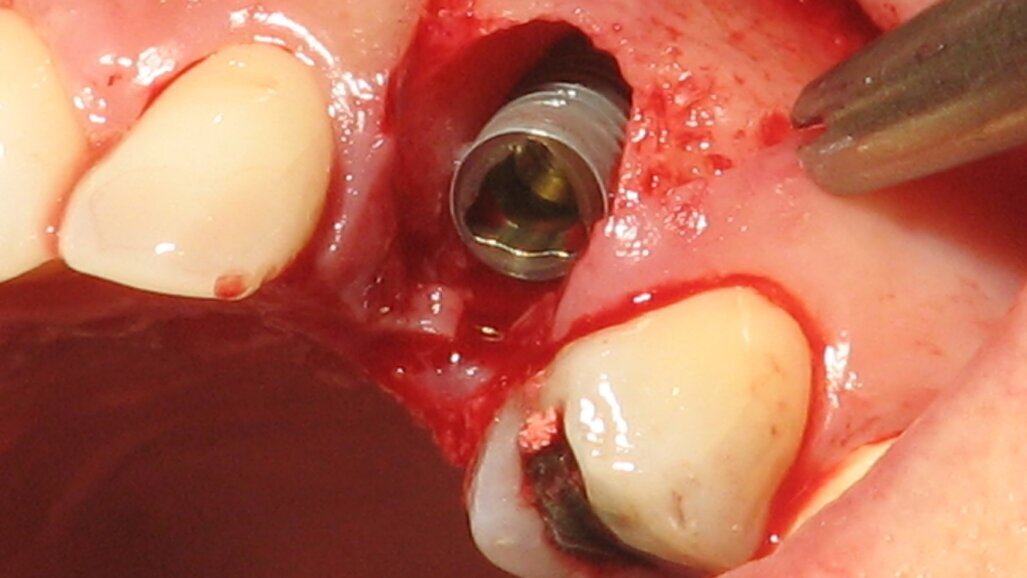

Komplikacije imedijatne ugradnje implantata su brojne i prvenstveno su uslovljene neadekvatnim odabirom slučaja i planom terapije. Estetski neuspesi implantata u frontalnim regijama predstavljaju jednu od najtežih komplikacija u savremenoj implantologiji. Razlozi za nastanak ovih komplikacija su: traumatska ekstrakcija zuba, nepravilno pozicioniranje implantata, neodgovarajući dijametar implantata, neadekvatna upotreba regenerativnih tehnika za nadoknadu koštanog i mekog tkiva kao i izrada neodgovarajućih protetskih nadoknada.

Nepravilno pozicioniranje implantata je greška koja se može prevazići upotrebom hirurškog stenta. Imedijatna ugradnja implantata upotrebom hirurške vođice i imedijatno opterećenje implantata nadoknadom kompjusterski isplaniranom i fabrikovanom pre same hirurške intervencije predstavljaju modalitet lečenja koji pacijentima pruža najbrže i najkomfornije rešenje.